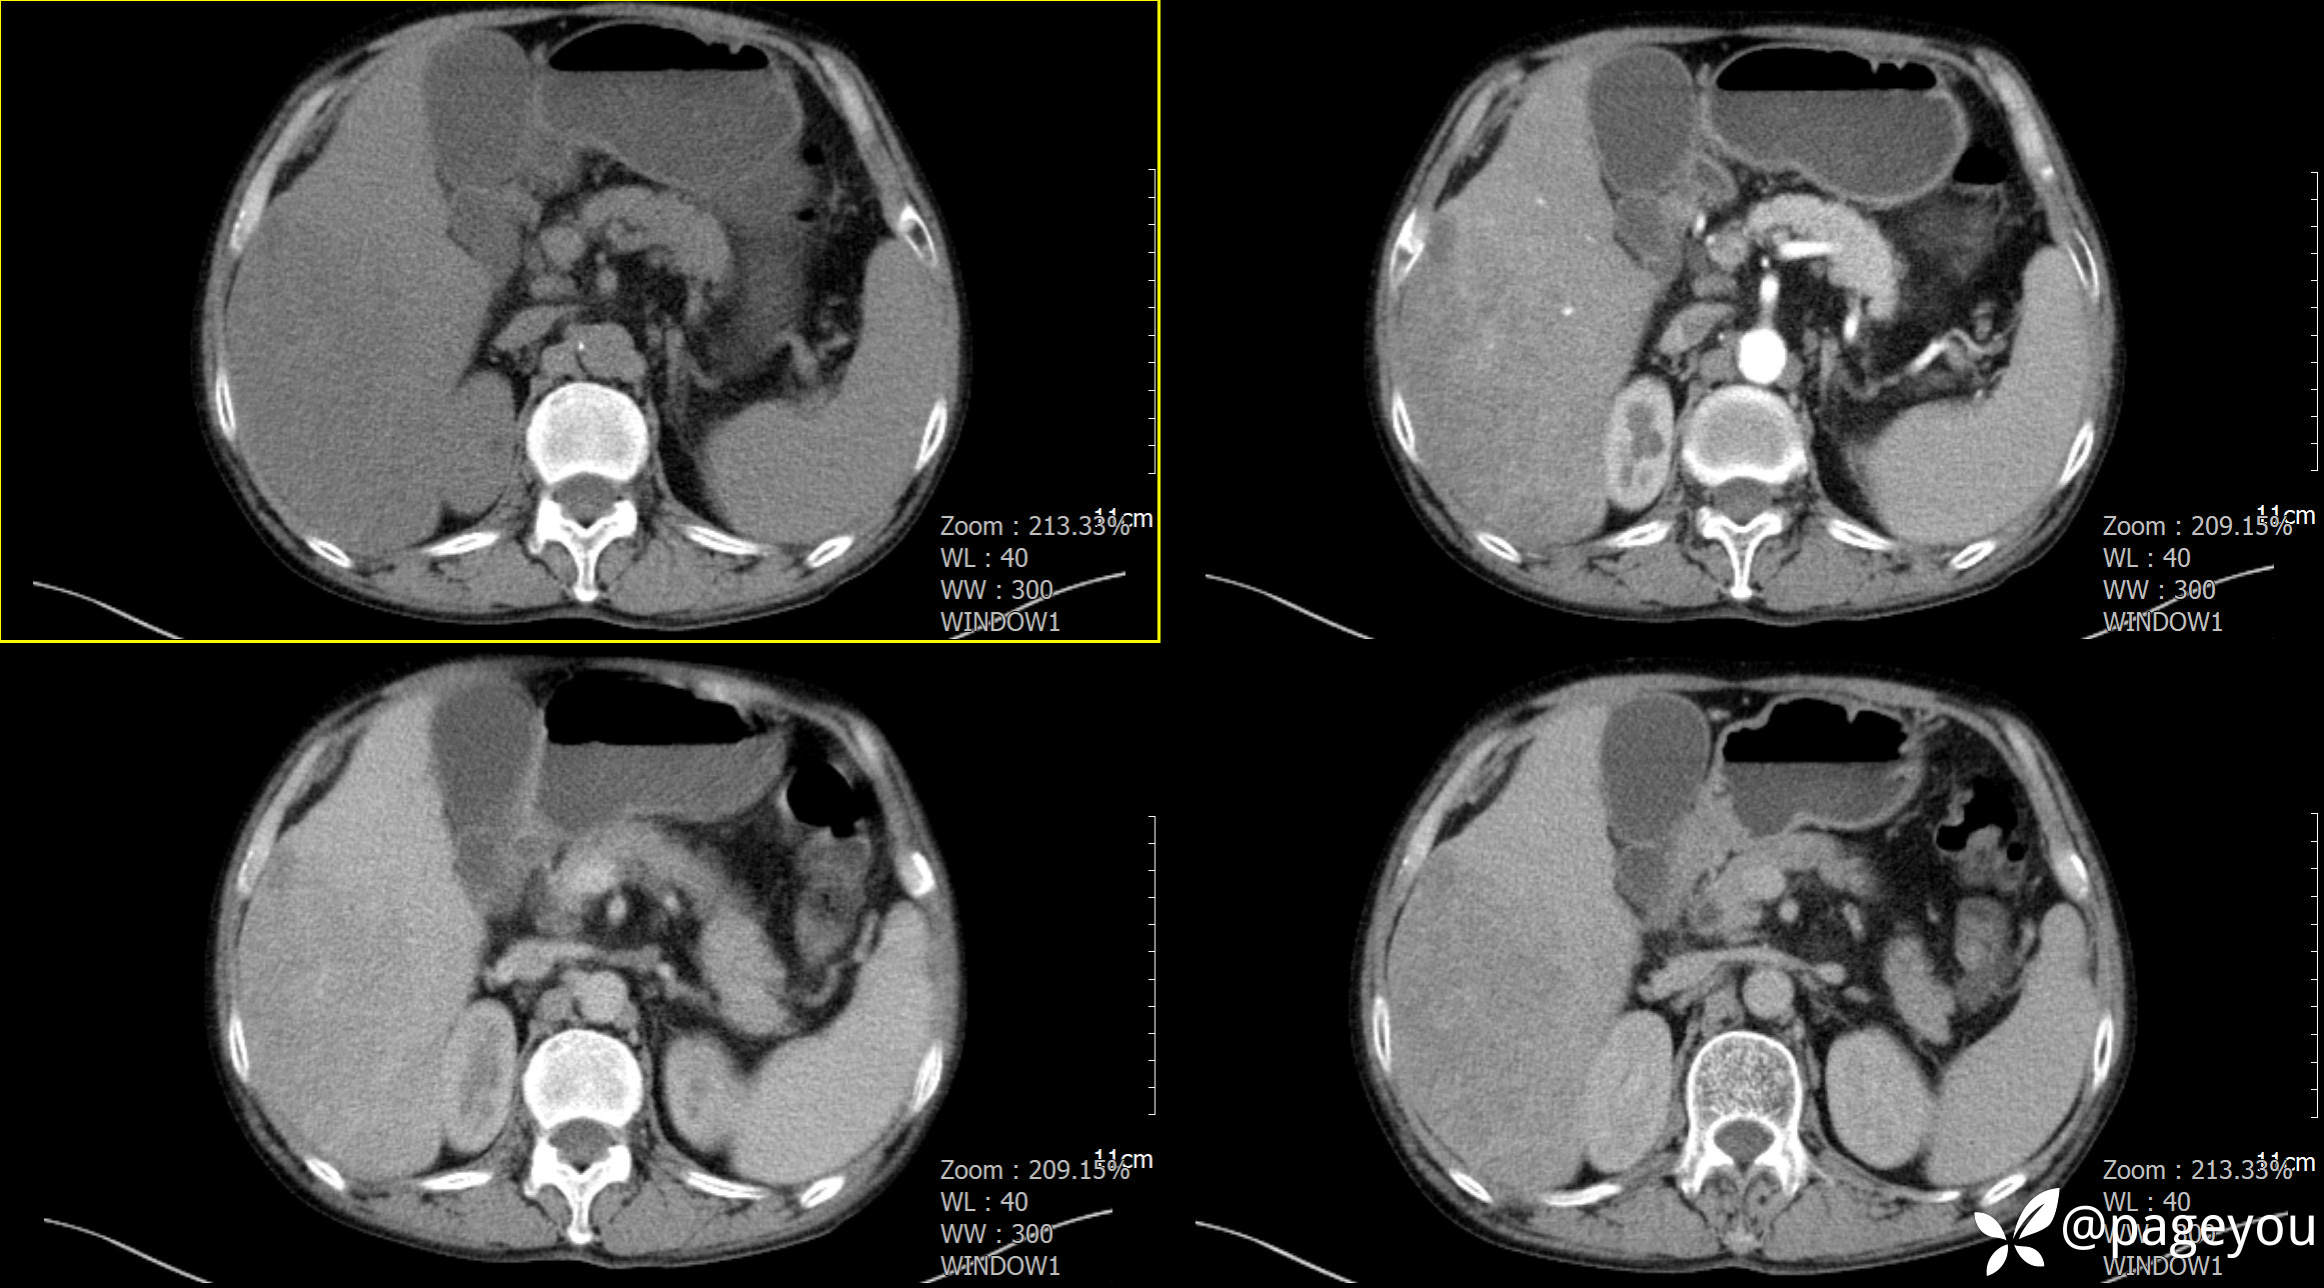

CT检查: